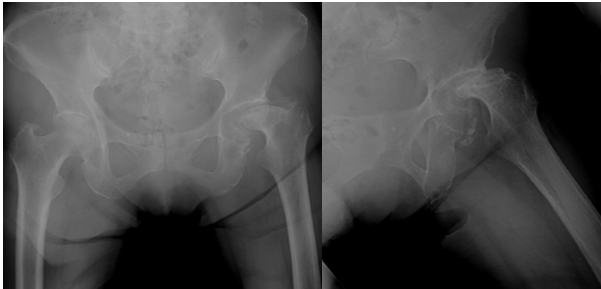

Her symptoms gradually worsened, and in October of year X, radiographs revealed progression of femoral head collapse (Fig. 3).

Figure 3: Radiograph obtained at the time of worsening pain, demonstrating progressive collapse of the left femoral head.

Although she was able sit in a wheelchair, her pain became intolerable. The patient and her family strongly requested surgical intervention for pain relief. Pre-operative computed tomography (CT) and MRI demonstrated metastatic bone destruction involving the left acetabulum and extending toward the ischium (Fig. 4).

Figure 4: Pre-operative computed tomography (CT) (left, axial view) and magnetic resonance imaging (MRI) (right, axial view). The axial CT view shows osteolytic metastatic destruction extending from the acetabulum toward the ischium (arrows). The axial T1-weighted MRI view demonstrates a metastatic lesion involving the superior acetabular dome, corresponding to the weight-bearing region (arrowheads).

Because the degree of acetabular destruction made placement of a cementless cup difficult, THA using the restoration GAP II reinforcement ring and a cemented acetabular cup was planned.